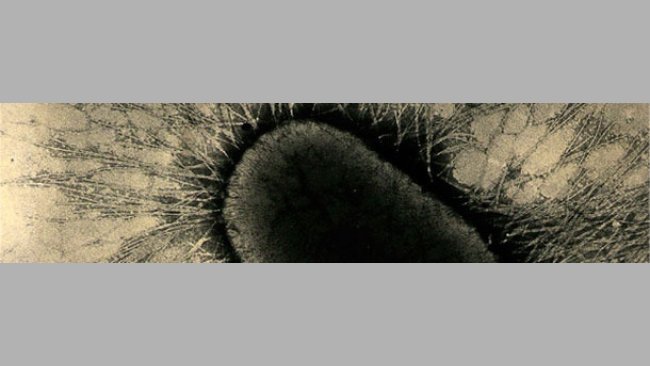

- Positivo: forte associazione causale se è in grado di dimostrare lesioni intestinali con E. coli che aderisce alle cellule epiteliali.